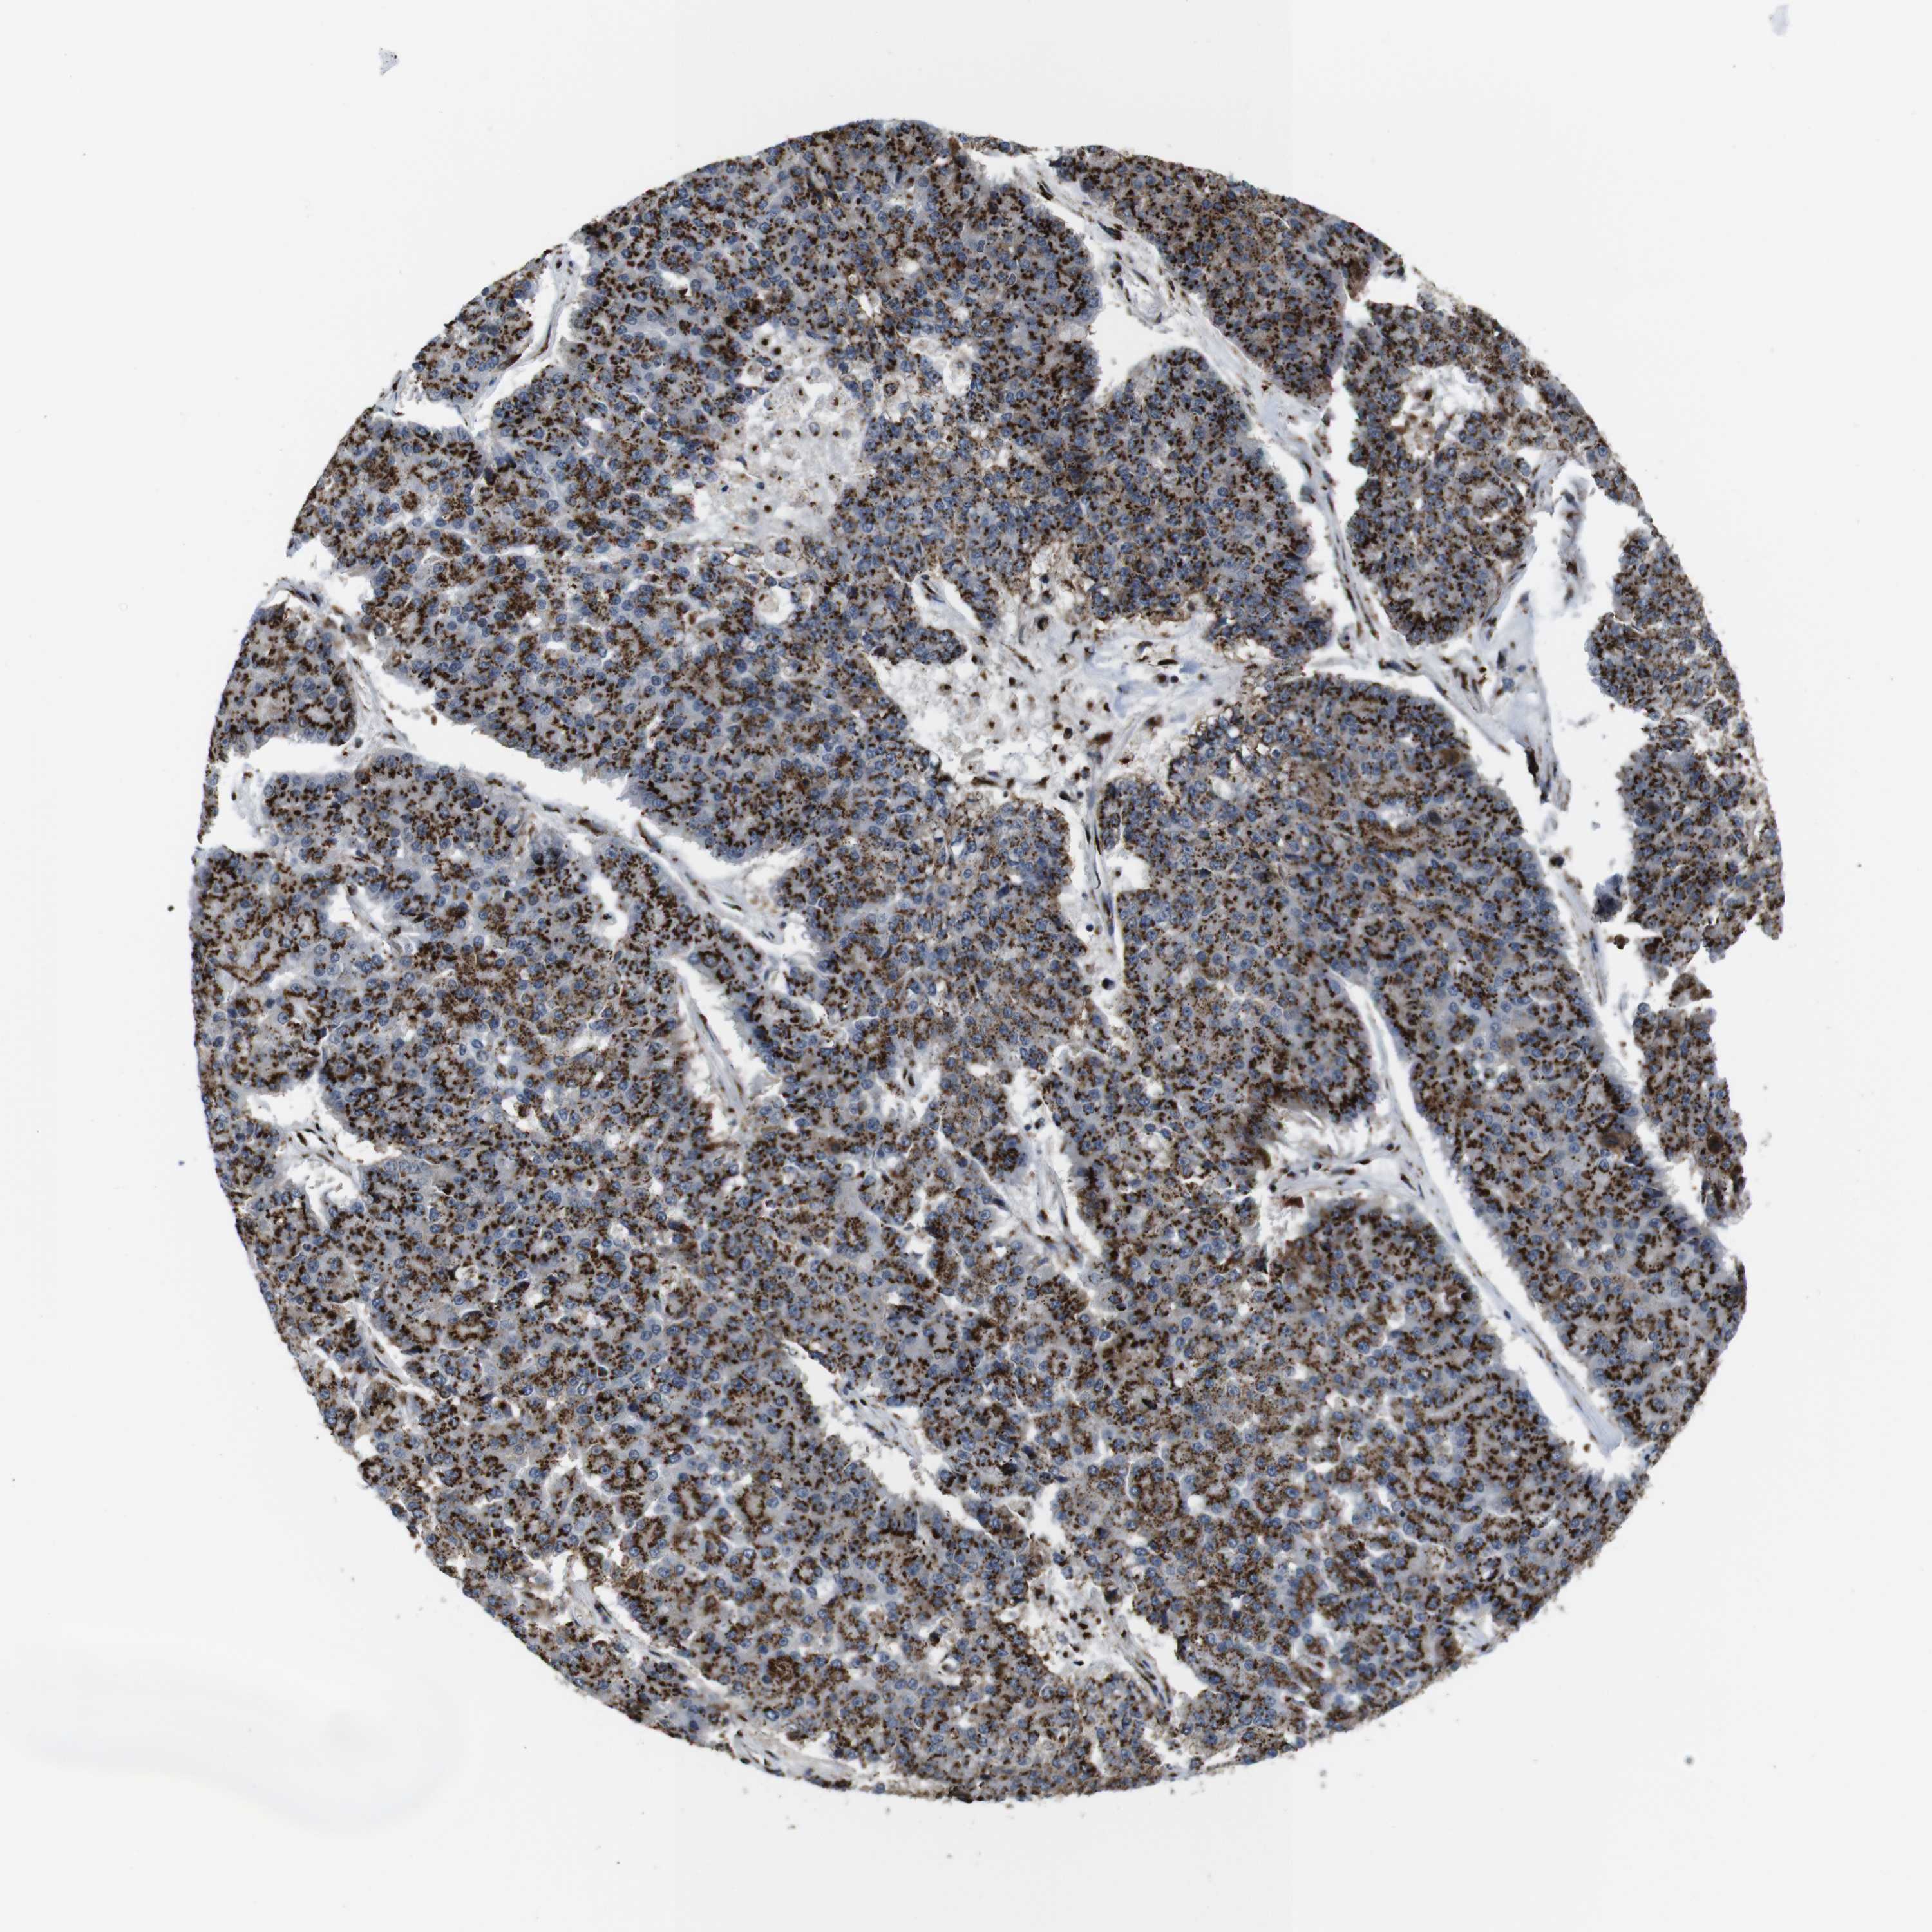

PANCREATIC CANCER - Protein expressioni

A mouse-over function shows sample information and annotation data. Click on an image to view it in a full screen mode. Samples can be filtered based on level of antibody staining by selecting one or several of the following categories: high, medium, low and not detected. The assay and annotation is described here.

Note that samples used for immunohistochemistry by the Human Protein Atlas do not correspond to samples in the TCGA dataset.

Antibody stainingi

Antibody staining in the annotated cell types in the current human tissue is reported as not detected, low, medium, or high, based on conventional immunohistochemistry profiling in selected tissues. This score is based on the combination of the staining intensity and fraction of stained cells.

Each image is clickable and will lead to virtual microscopy that enables deeper exploration of all samples and also displays staining intensity scores, fraction scores and subcellular localization as well as patient and tissue information for each sample.

Antibody HPA012609

Antibody HPA012723

Antibody CAB011489

Adenocarcinoma, NOS